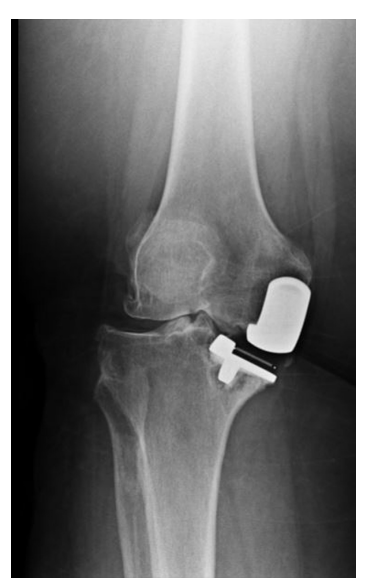

Kozinn和Soctt的经典限制性纳入标准在现代研究中得到了极大的扩展,这些研究表明UKA在年轻患者、肥胖患者、髌股疾病患者以及那些非常活跃的患者中取得了成功。无论如何,正确的患者选择对于确保UKA的成功结果仍然至关重要。对于所有前内侧OA(图1)、畸形可纠正(图2)、膝关节韧带完好、膝关节活动范围保留、屈曲挛缩小的患者,都可以考虑内侧UKA。

图1:计算机断层扫描显示前内侧骨关节炎。

图2:(A)站立正位X线片显示内侧关节间隙丢失。(B)外翻应力X线片显示可矫正的对齐和对侧关节空间的保存。